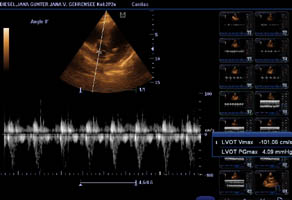

Herzultraschall von Lena vom Gehrensee zur Vermeidung von DCM

Durch Klick auf die Übersicht können die Herzdaten eingesehen werden.

Der Herzcheck ergab keinen Hinweis auf DCM.